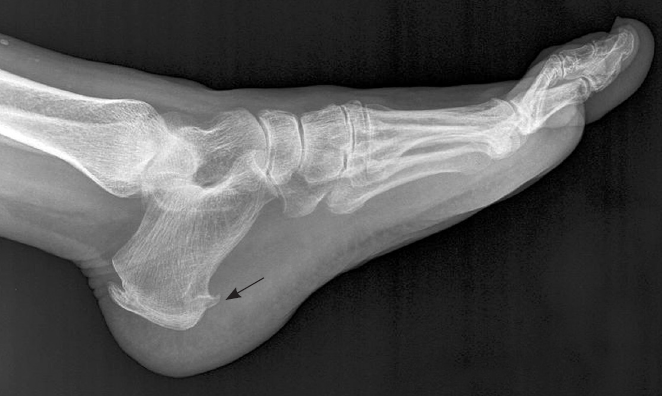

플랜타르 패시아염 (족저근막염)

- 발바닥의 아치에 위치한 두꺼운 섬유 조직인 족저근막이 염증이 생기는 질환입니다. 주로 장시간 서 있거나 걷는 경우, 혹은 비만으로 인해 과도한 압력이 가해져 발생합니다. 통증은 주로 아침에 일어났을 때 첫 발을 내딛을 때 가장 심하게 느껴지며, 점차 운동 후에도 나타날 수 있습니다.